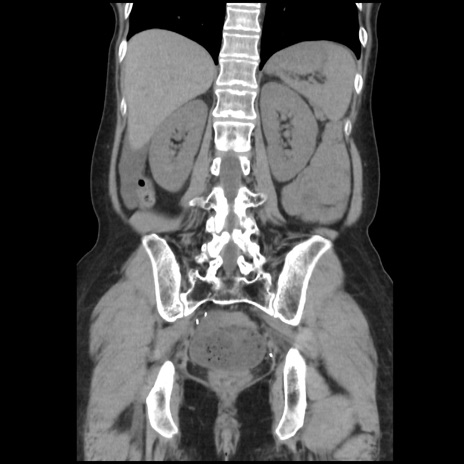

症例32(冠状断像)

【症例】40歳代 女性

【主訴】上腹部痛、嘔気・嘔吐

【現病歴】約9時間前頃から急に上腹部痛、嘔気、嘔吐が出現。改善しないため救急要請。

【既往歴】子宮頚癌(広汎子宮全摘術、放射線療法)、腸閉塞

【身体所見】腹部:平坦、軟、腸雑音亢進、上腹部を中心に腹部全体に圧痛あり。

【データ】WBC 8400、CRP 0.03